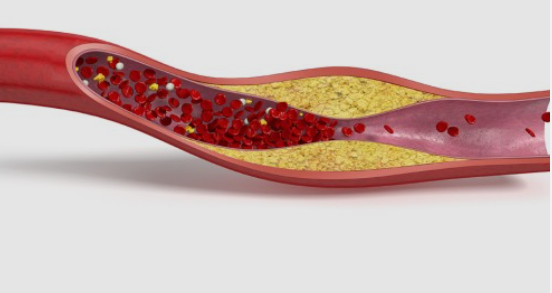

심근경색의 정의:

일반적으로 심장마비로 알려진

심근경색 전조증상은 심장 근육에 혈액을

공급하는 관상동맥 중 하나가

갑자기 막힐 때 발생합니다.

이 막힘은 일반적으로

죽상동맥경화반의 파열,

동맥의 콜레스테롤 및 기타 물질 축적으로 인해 발생합니다.

결과적으로 심장 근육으로의

혈류가 제한되어 허혈로 알려진 산소와 영양분의

부족을 일으켜 결국 손상을 초래합니다.

1.2 심장 마비란 무엇입니까?

심근경색이라고도 알려진

심장마비는 심장 근육에 혈액을

공급하는 관상동맥 중 하나가 갑자기

막힐 때 발생합니다.

이 폐색은 일반적으로 죽상동맥경화반의 파열,

동맥의 콜레스테롤 및 기타 물질 축적으로

형성된 혈전으로 인해 발생합니다.

이 막힘은 심장 근육으로의 혈류를 제한하여

산소와 영양분 부족으로 이어져 시간이

지남에 따라 손상을 일으킵니다.